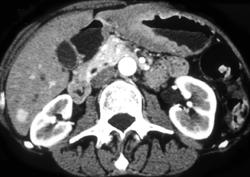

Antral Carcinoma With Adenopathy